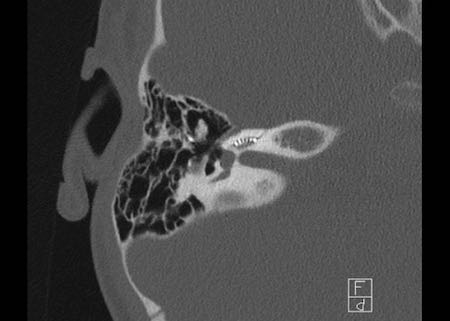

Bên trái là hình ảnh của một bé gái 2 tuổi.

Các hình ảnh từ kết quả chụp CT được thực hiện trước khi cấy ốc tai điện tử.

Quan sát thấy dị dạng nhẹ ở đỉnh ốc tai – không có sự phân tách giữa vòng thứ hai và vòng thứ ba, và trụ ốc tai xương vắng mặt.

Cống tiền đình bình thường.